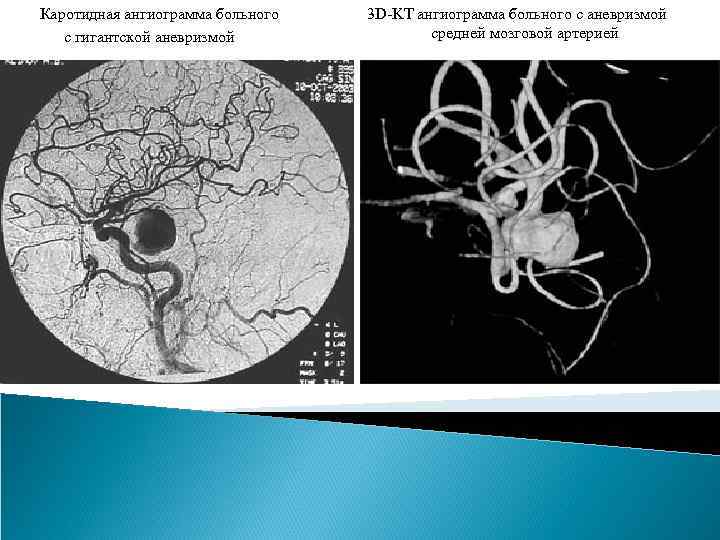

Методы лечения аневризм сосудов головного мозга. Определение аневризмы сосудов мозга является прямым показанием к проведению лечения, которое является исключительно хирургическим: - клипирование аневризмы (открытые вмешательства), - эндоваскулярное вмешательство Клипирование аневризмы. Целью внутричерепного (открытого) вмешательства на аневризме является выключение ее из кровотока при сохранении проходимости несущего и окружающих сосудов, удаление крови из субарахноидального пространства. Эти операции относятся к ряду наиболее сложных операций в нейрохирургии. Операция должна быть минимально травматична, что обеспечивается выполнением оптимальных хирургических доступов, микрохирургической техники и одномоментным клипированием шейки аневризмы. Для выполнения операции используется операционный микроскоп, специальный микрохирургический инструмент. При открытом вмешательстве, проведенных в условиях специализированных отделений крупных центров, летальность после операции в остром периоде кровоизлияния составляет 8 -16%, а в хроническом периоде кровоизлияния (через 1 месяц после него) – не более 2 -3%.